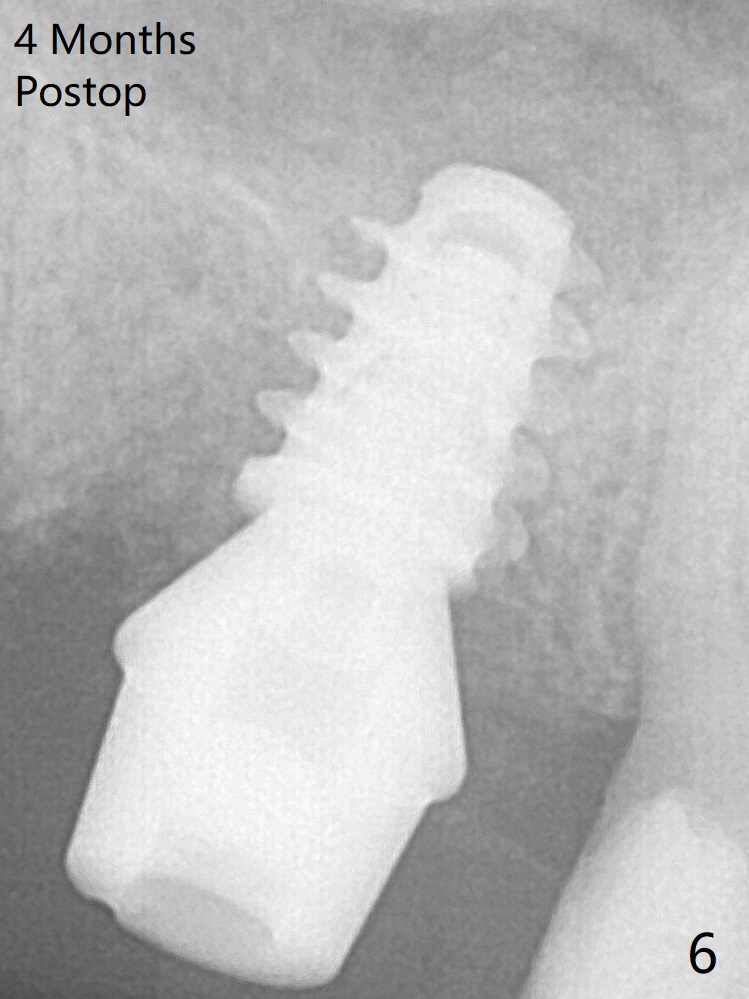

The implant is mobile 4 months postop (Fig.6).  A 6x2 mm healing abutment is placed next.